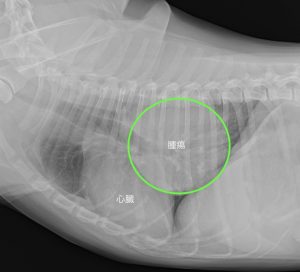

今回ご紹介するわんちゃんは咳が出るようになりかかりつけ動物病院を受診したところレントゲン検査で右肺後葉に大きな腫瘍が見つかり、当院を紹介来院しました。

より詳しい診断のためCT検査を行いました。

腫瘍は心臓よりも大きく、右肺後葉に発生していました。

他の肺に転移は認められずリンパ節への転移もありませんでした。